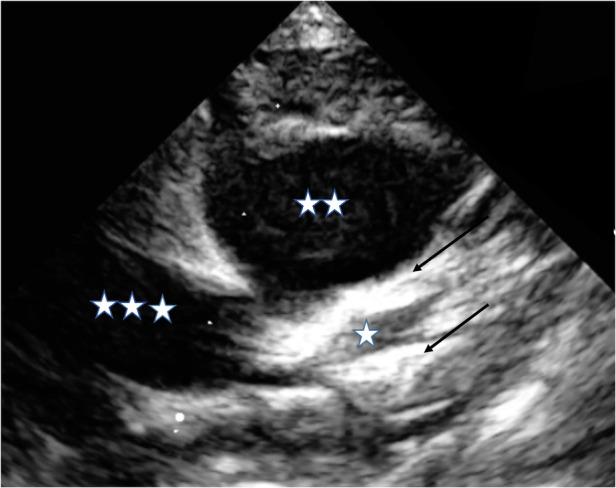

A small group of patients with Kawasaki disease (KD) demonstrates resistance to standard therapy, putting them at high risk for an unfavorable prognosis, especially regarding coronary artery aneurysms. Although adding corticosteroids to first-line i.v. immunoglobulins (IVIGs) is considered beneficial, and despite timely treatment initiation, very young infants, in particular, can present an unfavorable clinical course. We report on a 3-month-old boy with a clinically severe KD phenotype involving the early development of giant coronary artery aneurysms. Because of his poor response to the first course of IVIG and prednisolone, we administered infliximab. His clinical condition improved after that, and his temperature dropped. Inflammatory markers however did not recover completely, and he remained subfebrile. In addition, as the coronary artery dimensions deteriorated, a second IVIG course was administered and prednisolone continued at the initial dosage. Although fever and routine inflammatory parameters normalized, close follow-up investigations revealed both still increasing coronary artery dimensions and renewed rise in inflammatory parameters, necessitating two more infliximab administrations in addition to continuous prednisolone. Because of the coronary artery dimensions (left anterior descending artery, 4.9 mm, Z-score 11.1; right coronary artery 5.8 mm, Z-score 15.5), dual platelet inhibitory therapy with ASA and later clopidogrel combined with low-molecular heparin was indicated. Four weeks after his initial KD diagnosis, we detected no renewed increase in inflammatory markers; at that time, we observed a slight reduction in coronary dimensions. In summary, despite timely guideline-fulfilling therapy, the prolonged clinical course of this very young infant with KD entailing the development of giant coronary artery aneurysms makes us question whether this age group may benefit from early, even more intense therapy.

一小部分川崎病(KD)患者对标准治疗表现出耐药性,这使他们面临不良预后的高风险,尤其是在冠状动脉瘤方面。尽管在一线静脉注射免疫球蛋白(IVIG)中添加皮质类固醇被认为是有益的,而且尽管及时开始治疗,但特别是非常小的婴儿可能会出现不良的临床病程。我们报告了一名3个月大的男孩,其临床症状严重,患有KD,伴有巨大冠状动脉瘤的早期形成。由于他对第一疗程的IVIG和泼尼松龙反应不佳,我们给予了英夫利昔单抗。此后他的临床状况有所改善,体温下降。然而,炎症标志物并未完全恢复,他仍有低热。此外,随着冠状动脉尺寸恶化,给予了第二疗程的IVIG,并继续按初始剂量使用泼尼松龙。尽管发热和常规炎症参数恢复正常,但密切的随访调查显示冠状动脉尺寸仍在增加,炎症参数再次升高,因此除了持续使用泼尼松龙外,还需要再给予两次英夫利昔单抗。由于冠状动脉尺寸(左前降支动脉,4.9 mm,Z评分11.1;右冠状动脉5.8 mm,Z评分15.5),因此建议联合使用阿司匹林和氯吡格雷进行双重血小板抑制治疗,并联合低分子肝素。在他最初被诊断为KD四周后,我们未检测到炎症标志物再次升高;此时,我们观察到冠状动脉尺寸略有减小。总之,尽管及时进行了符合指南的治疗,但这名患有KD且伴有巨大冠状动脉瘤形成的非常小的婴儿的临床病程延长,这使我们质疑这个年龄组是否可能从早期、甚至更强化的治疗中获益。